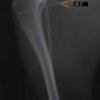

術前左後肢側面像

本症例は、走った後に左後肢を挙上していることを主訴に来院されました。触診時に左膝関節のクリック音を聴取、レントゲン検査にて左脛骨の前方変位が認められました。術中に、前十字靱帯の断裂及び内側半月板の損傷、内側の軟部組織の顕著な腫脹を確認。半月板切除、TPLOを実施しました。周囲組織への炎症の波及もあったため回復に時間を要しておりますが、徐々に跛行頻度は減少傾向にあり、現在も経過観察中です。術前に約29°あったTPAは術後に約10°まで矯正されました。

術前写真

手術前後のTPA(脛骨高平部の角度)を測定しています。

約29°から約10°へ矯正されています。